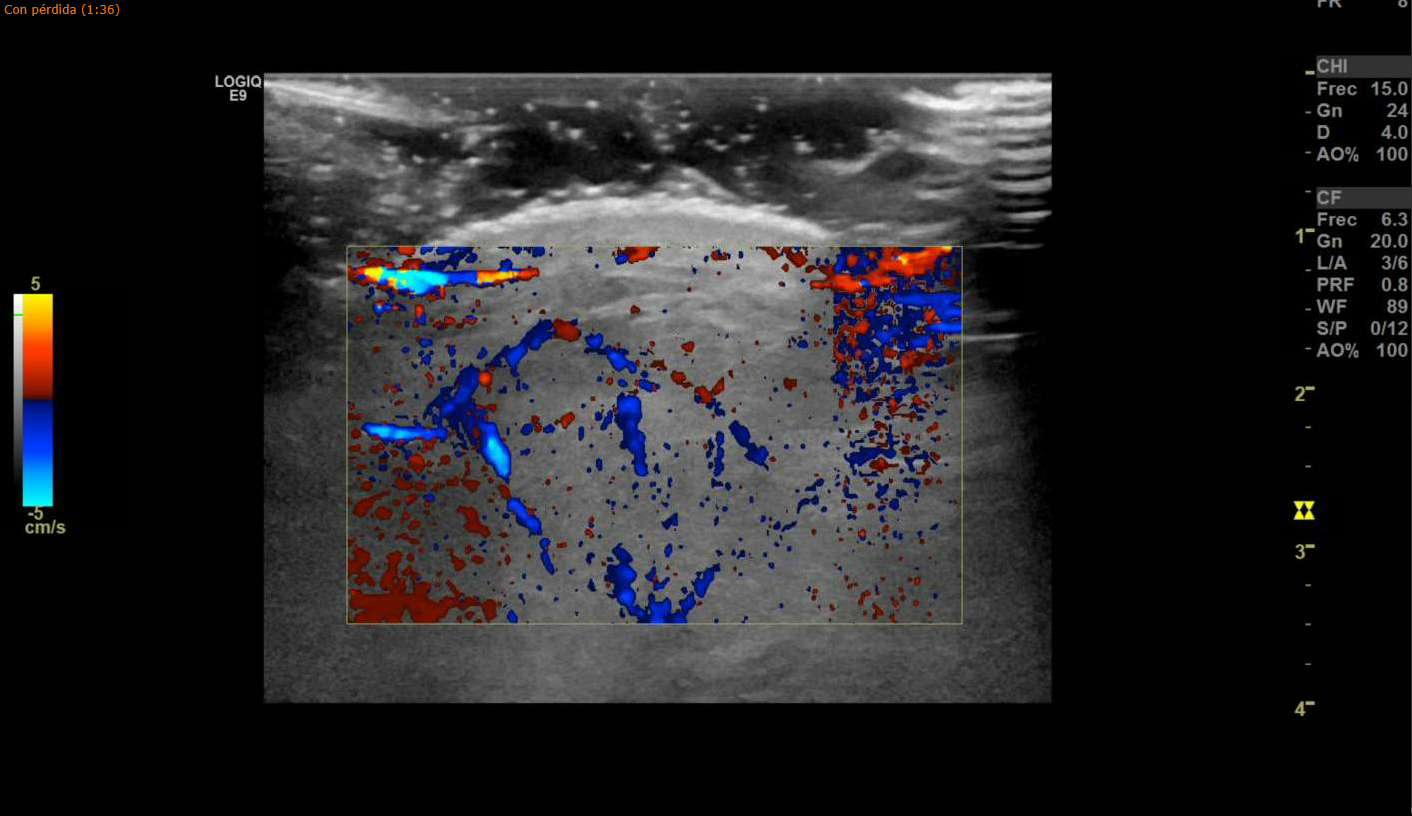

Para confirmar la sospecha se le realiza ecografía testicular, apreciando colección hemática en borde superior de bolsa escrotal izquierda, conservando flujo arterial y venoso. Impresiona de línea hipoecogénica que atraviesa el parénquima testicular, correspondiendo con rotura traumática de testículo izquierdo.